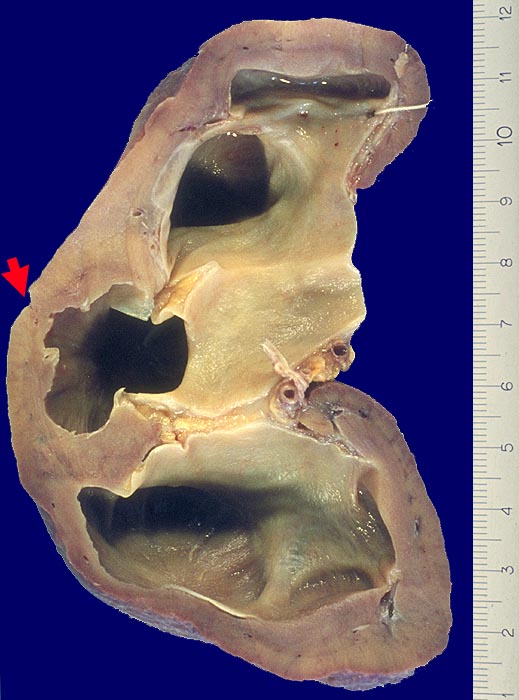

Morphologie:

Die Nieren sind mehr oder weniger stark verkleinert. Die Oberfläche ist durch breitbasige und U-förmige narbige Einziehungen über dilatierten oder deformierten Nierenkelchen grob gebuckelt. Die Narben sind verschieden gross und aufgrund der starken Vaskularisation rot gefärbt. (Vaskuläre Narben sind dagegen weiss und scharf begrenzt). Das Endstadium bildet eine fein granulierte Schrumpfniere (=totale pyelonephritische Narbenniere). Die Mark-Rindengrenze ist verwaschen. Die Narben sind auf Schnitt keilförmig und reichen mit der Keilspitze bis ans Nierenbecken. Die Nierenbeckenschleimhaut ist stark verdickt und eventuell gerötet. Papillennekrosen sind besonders bei Diabetikern und Analgetikanephropathie häufig.

• Grobhöckrige Nierenoberfläche wegen narbigen Einziehungen.